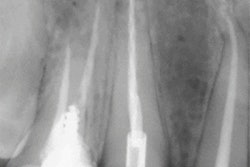

The 41-year-old was sent home with medication after he underwent x-rays and blood tests. However, his flu-like symptoms persisted, and he developed a blood blister on his toe. Clinicians diagnosed the blister as a Janeway lesion, which is another sign of infective endocarditis.